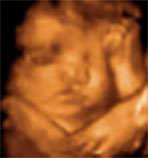

怎样选择排畸时间?| 仪器 | 美国E8四维 | 普通四维 |

| 图像 | ![]() |

| 画质 | 立体动态成像,画质比较清晰 | 动态成像画质普通 |

| 优势 | 多方位、角度地观察孕宝宝的生长发育,对孕妇潜藏的疾病进行检测,无辐射。 | 较准确地动态呈现腹中胎儿的生长发育情况 |

| 劣势 | 目前影像科分辨率高的 | 清晰度稍差,数据分析能力较弱 |